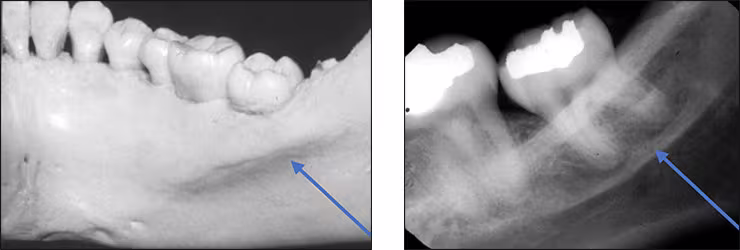

Submandibular fossa – The submandibular fossa is a depression in bone on the lingual aspect of the posterior mandible. The fossa is located bilaterally below the internal oblique ridge or mylohyoid line. This concavity is where the submandibular salivary gland rests. The submandibular fossa presents as a diffuse bilateral radiolucency typically with few trabeculae. It can appear unusually radiolucent, enticing the novice clinician into thinking a bony lesion is present. The submandibular fossa is recorded on premolar and molar periapical images. This structure is also referred to as the submandibular gland fossa or mandibular fossa.

Lower border – The lower border of the mandible appears as a radiopaque band of dense cortical bone demarcating the inferior aspect of the mandible. This structure can be observed on any mandibular periapical view, especially when the x-ray beam angulation is excessive.